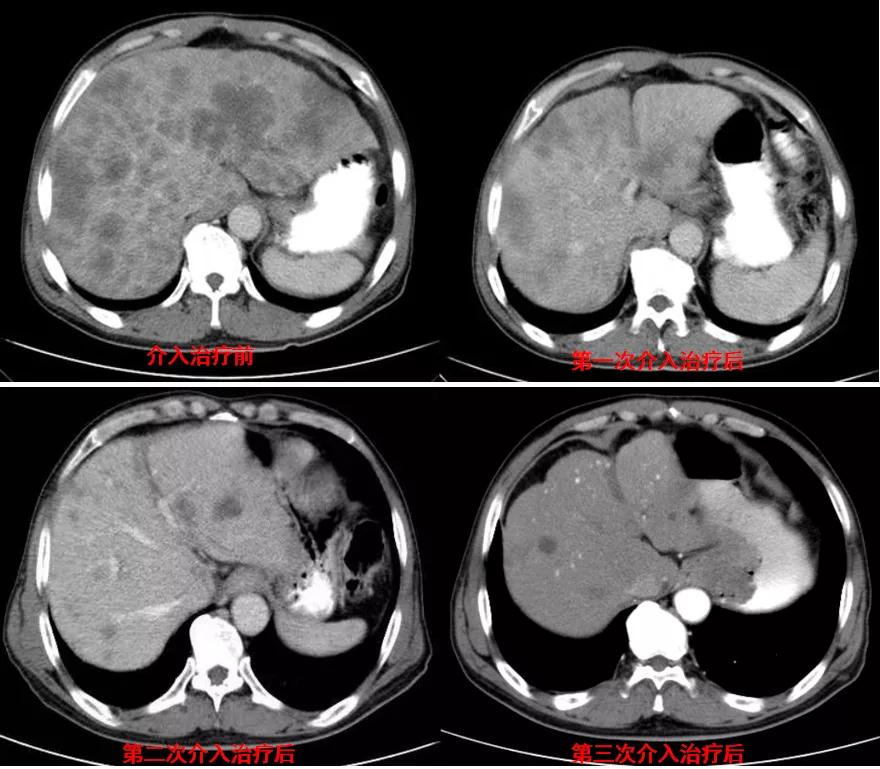

诊治经过:2020年11月25日患者行经皮动脉化疗灌注栓塞术(铂类+氟尿嘧啶);2020年11月30日免疫组化及基因检测结果为:ERBB-2扩增(9倍),VEGFR未突变,MSI微卫星低度不稳定,错配修复蛋白部分缺失(dMMR),MSH2(+弱),MLH1(-),MSH6(+),PMS2(-),CDX2(-),Villin(+),CK8/18(+),Ki67(5%+),CD56(-),Syn(-),CgA(-);患者为HER2阳性,患者肝脏病灶很多,残余正常肝脏体积小,需要寻找对肝功能影响小且抗瘤效果明显的治疗,因此联合吡咯替尼进行系统治疗。2020年12月14日复查结果提示肝脏病灶明显缩小(PR)。结果见图2。

图2

诊治经过:2020年12月16日患者行第二次经皮动脉化疗灌注栓塞术(铂类+氟尿嘧啶)治疗,并继续联合吡咯替尼治疗。结果见图3。

图3